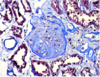

What disease process is seen here?

Membranoproliferative - combination of BOTH increased cell number, inflammation, and thickening of basement membrane